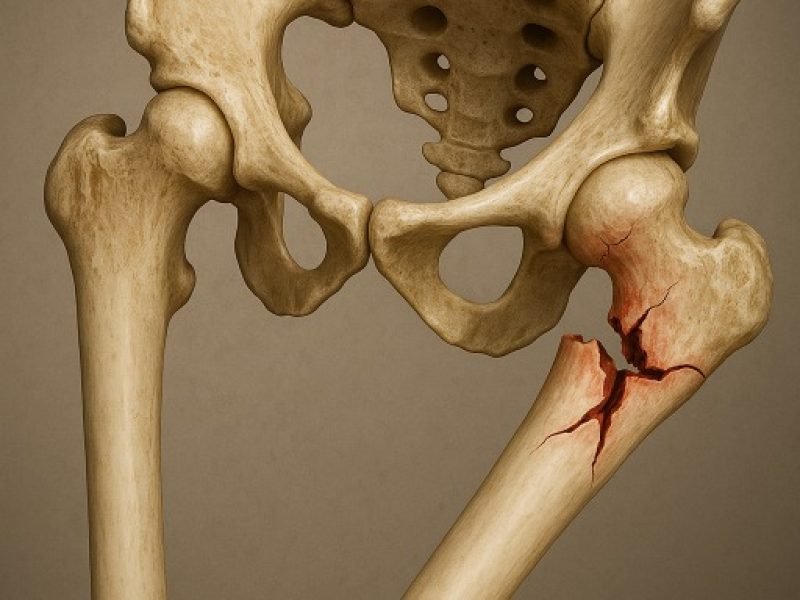

We provide specialized surgical care for pelvic injuries, using precise techniques to stabilize the pelvic structure and promote a safe, complete recovery.